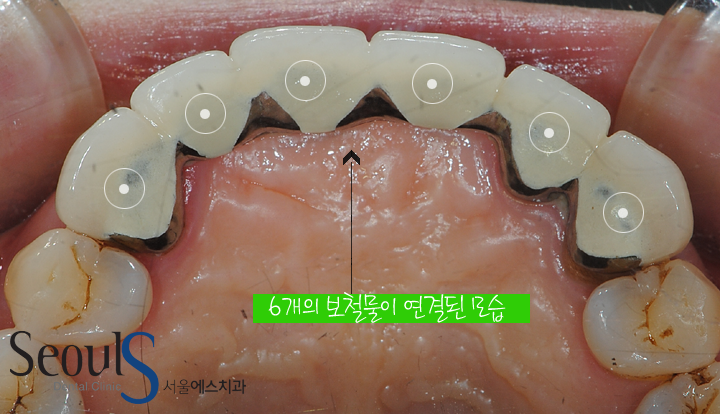

6개의 보철물이 연결된 앞니브릿지 치료를 타치과에서 받았던 분입니다

브릿지를 잘 사용하시다

브릿지에 틈이 생겨 충치와 염증이 진행되었습니다

증례를 보면서 설명드리겠습니다

앞니 3개가 빠져서 빠진 치아 주변 3개의 치아를 다듬어서

6개의 보철물을 씌웠습니다

뒷면 모습입니다

6개의 보철물이 연결된 모습이고

잇몸 부분을 보시면 염증이 진행되고 있습니다

브릿지를 지지해주는 치아에 문제가 생긴것을 예상할 수 있습니다